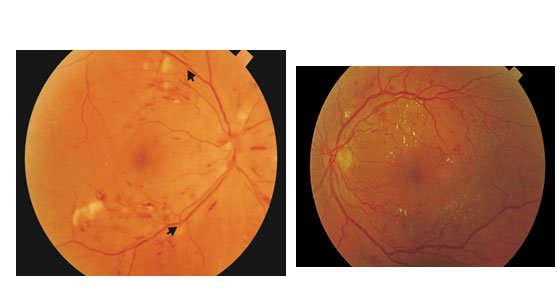

- Retinopatia Diabética Proliferativa: é a fase mais avançada e perigosa da retinopatia diabética, onde há formações de novos vasos na retina e no globo ocular para tentar combater a falta de oxigêneo gerada pelas hemorragias.O grande problema e que esses novos vasos são muito frágeis e se rompem e aumentam ainda mais a vazamento de sangue e líquido causando danos graves a visão.

- Retinopatia Diabética Não Proliferativa Severa: Há extensas áreas de bloqueio vascular com extravazamento de sangue e líquido em maior quantidade, com maior risco de complicações.

Retinopatia Diabética Não Proliferativa Moderada: áreas mais extensas de dilatação vascular com extravasamento de sangue e bloqueio vascular.

- Retinopatia Diabética Não Proliferativa Leve: é o inicio da retinopatia diabética onde há poucas áreas de dilatação vascular dos vasos sanguíneos da retina.